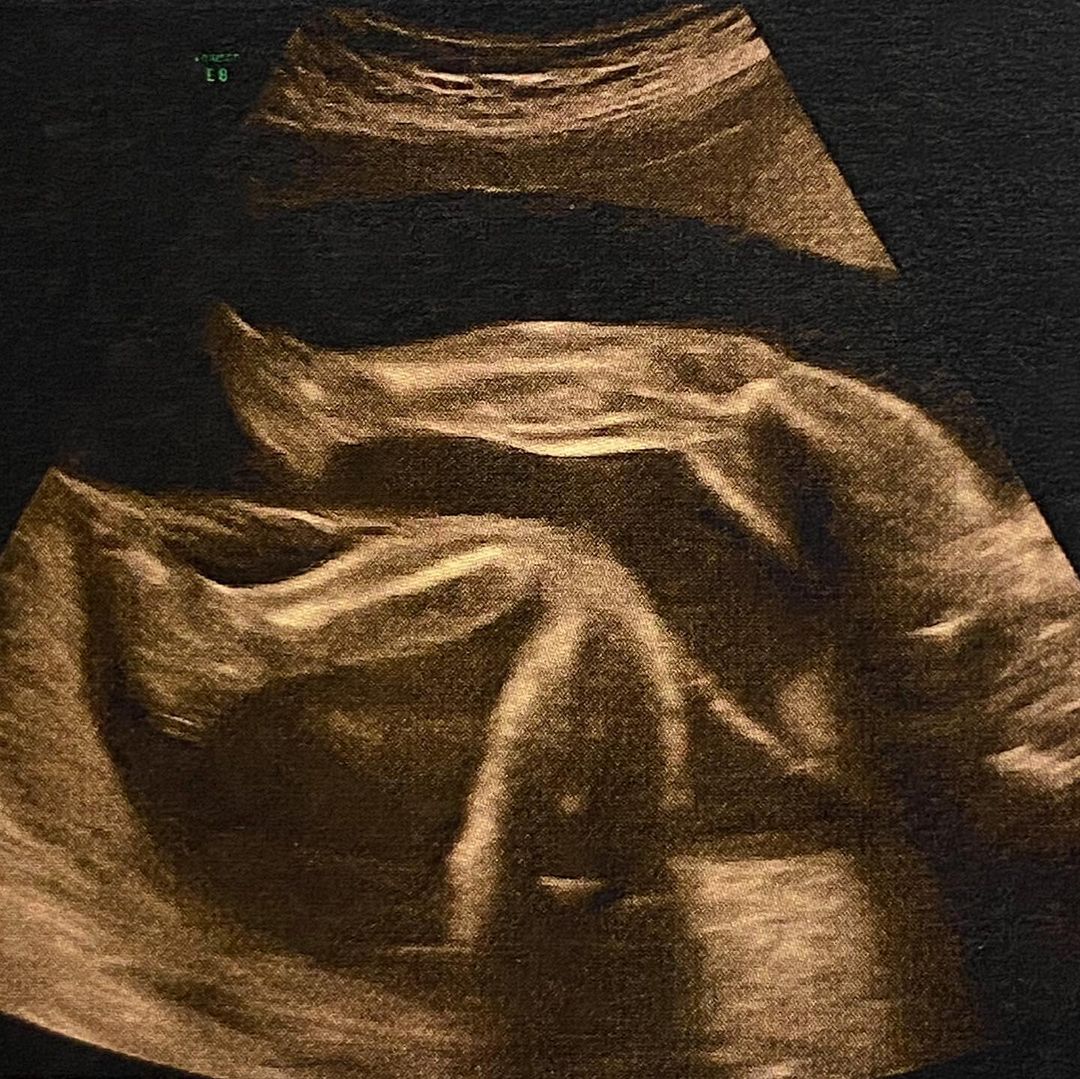

“La segunda es la foto más tierna que verás hoy”, escribió la actriz.

La actriz Rocío Toscano compartió una ecografía de los mellizos que espera, donde se ven sus piernas a través de sus redes sociales.

"La segunda es la foto más tierna que verás hoy. Aquí estamos... los 4", escribió junto a las postales.